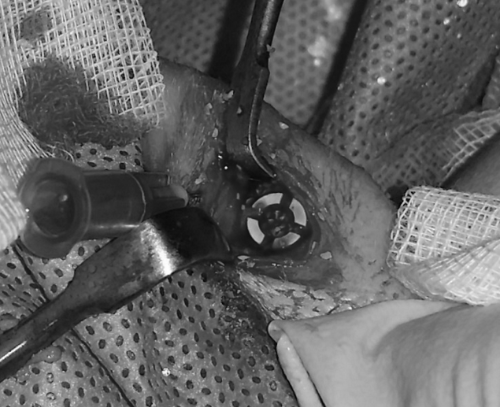

험은 총 8 마리 토끼를 대상으로 진행하였습니다. 토끼 무릎에 털을 깎은 다음, 정형외과 전공의가 실제 수술방에서 늘 하던 방식대로 토끼 다리의 소독을 진행하였습니다. 첫 수술의 집도는 안면환 교수님께서 직접 하셨습니다. 그리고 시범 뒤에 전공의 대학원생들도 수술을 집도하였습니다. 무릎 관절 위아래로 피부 절개를 시행하고, 치과용 드릴을 이용하여 구멍을 만들어서, 골대체 물질을 채운 원통을 삽입한 뒤 수술을 종료하였습니다.

phd2.png 사진 2. 골 재생 연구를 위한 실험 과정. 실제 수술 사진.